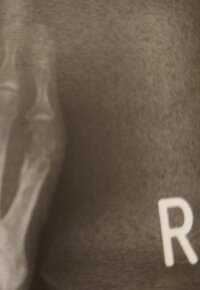

19日のブログで、秋野は「5月に折った右足の骨」と切り出し「やっと、完治しました」と報告。「今年は色々ありますが…」「ひとつずつクリァーにしていきます」とコメントし「ほんとに忙しい年です。治ってくれて良かった!」」と前向きにつづった。

20日に更新したブログでは「昨日、足のレントゲンを撮るので、久しぶりに外来に行って」と説明。抗がん剤の点滴をしている女性が辛そうにしている様子を見かけたそうで「何日目なのかな?痛くないように、辛くないようにお薬コントロールできればいいのになぁ」とコメント。「癌の痛みや苦しみが消えるように願います」と祈るようにつづった。